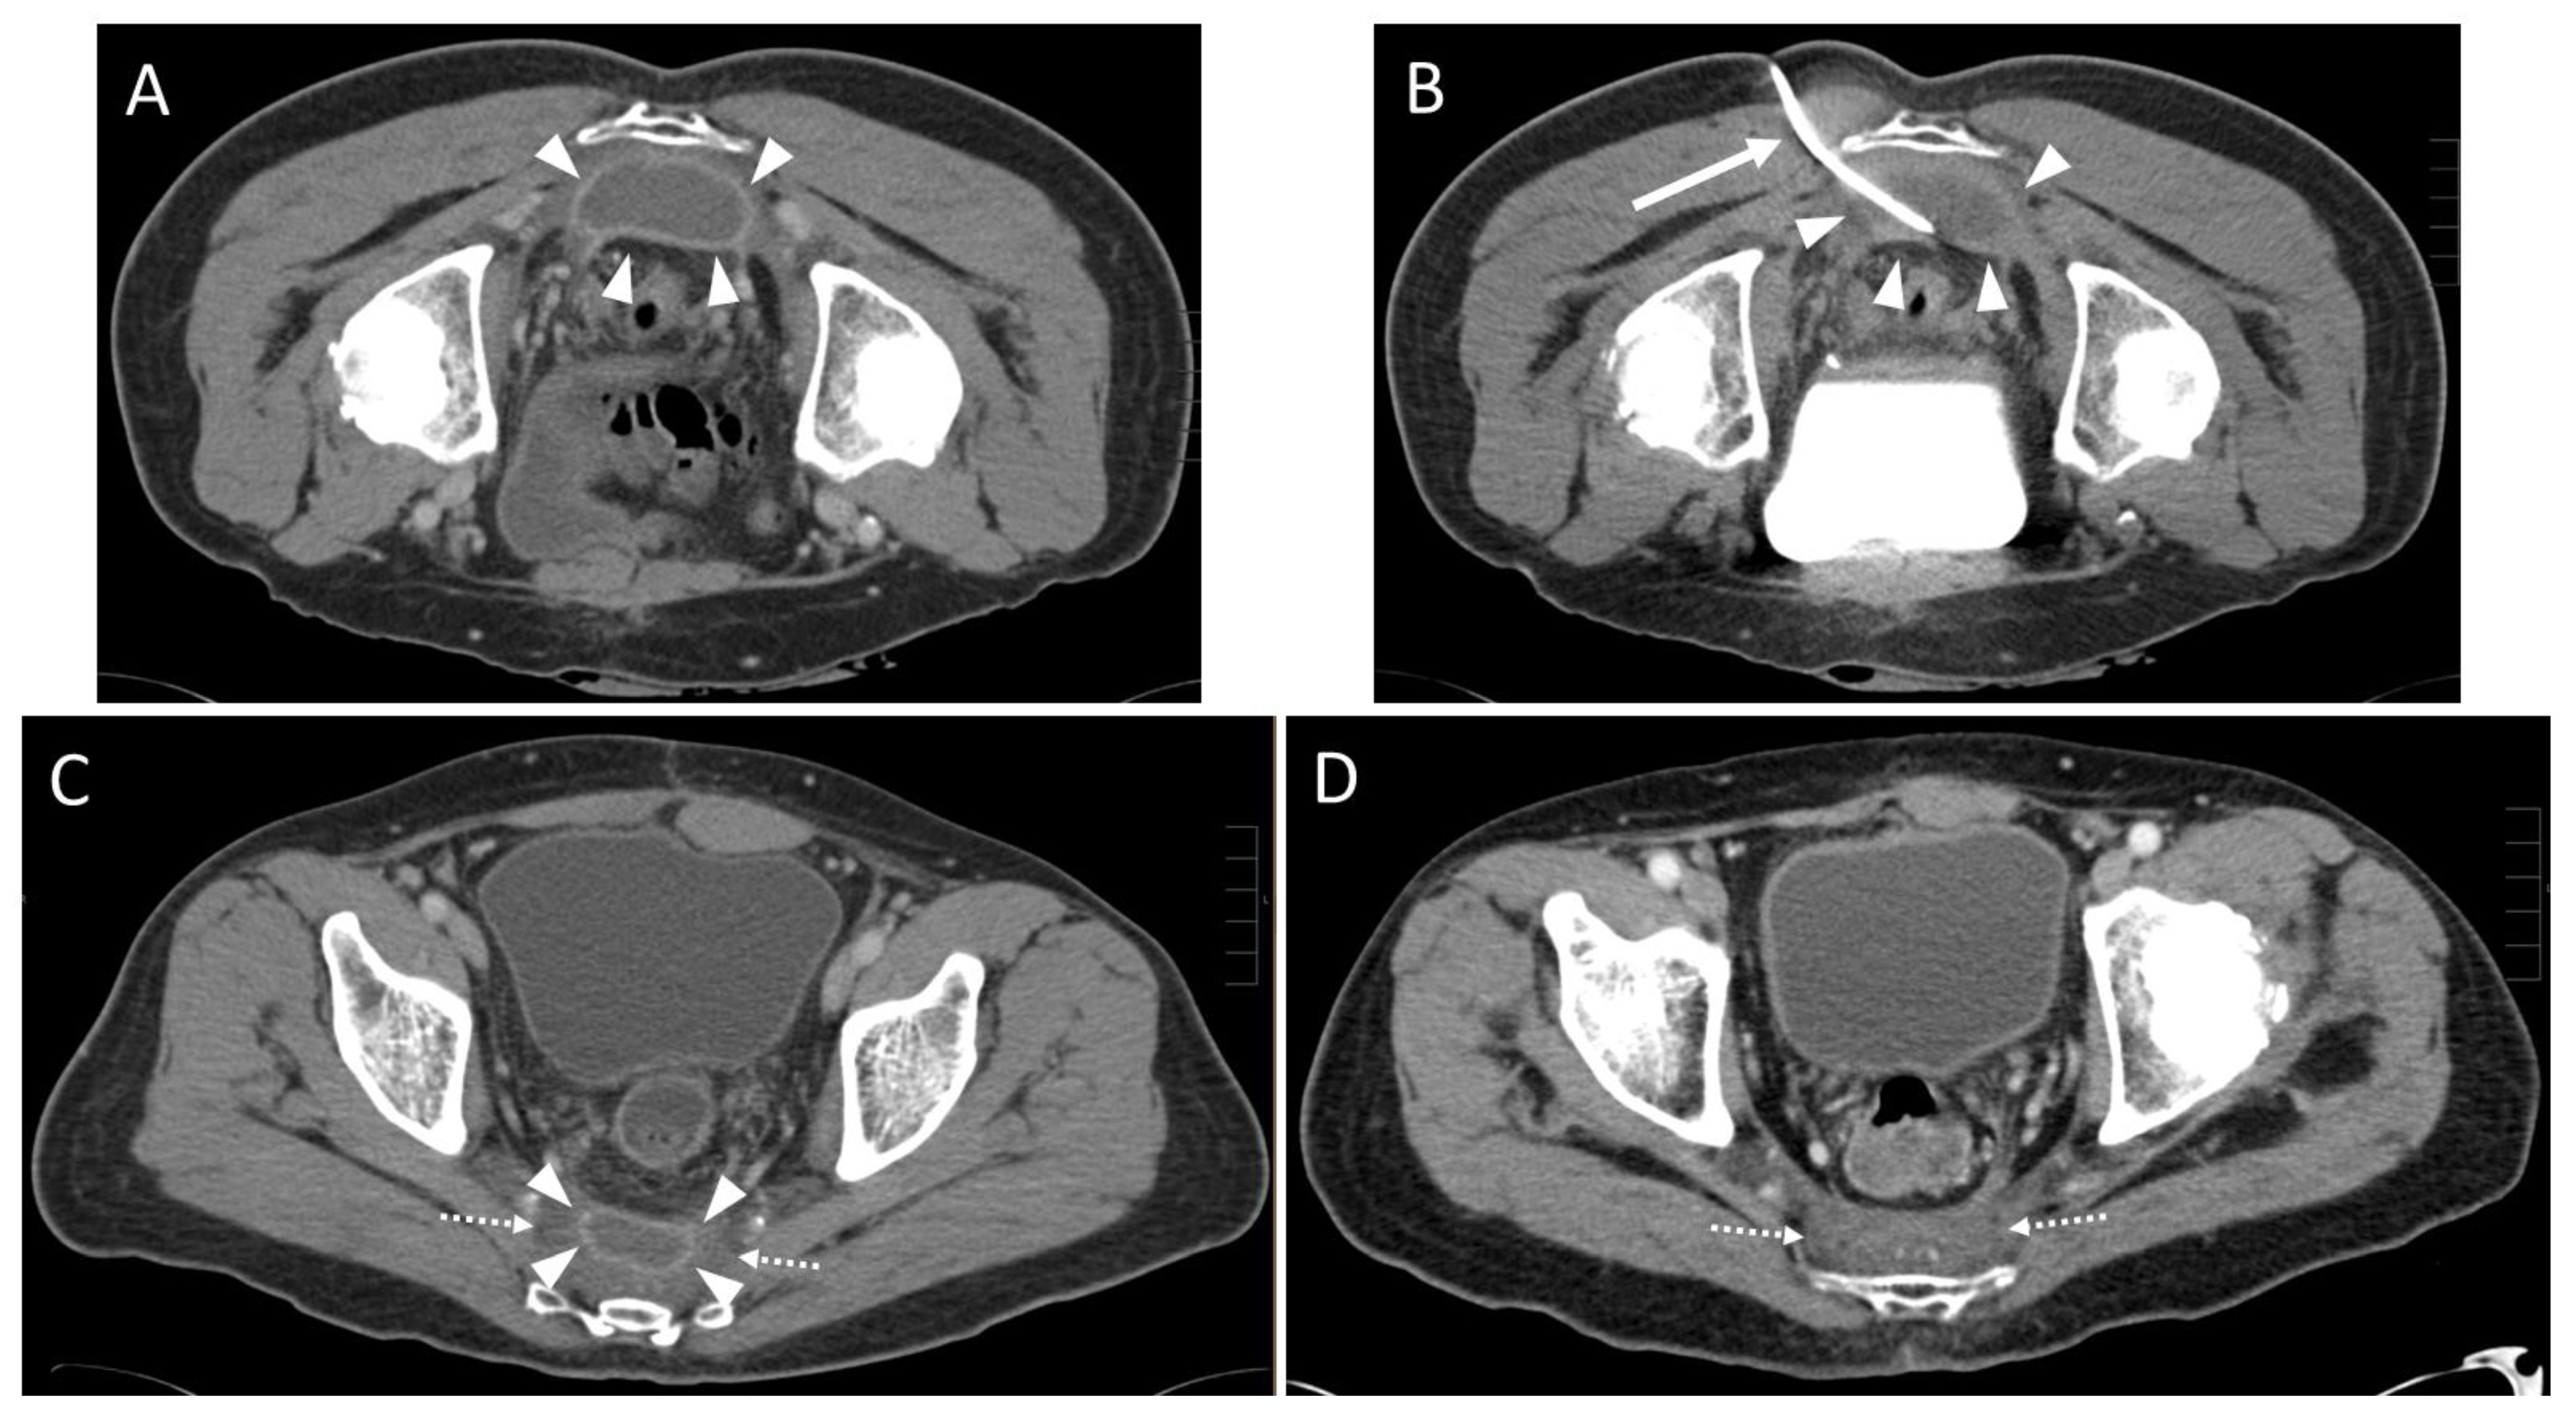

3.2. Pre- and Peri-Interventional Analysis

| Approach | |

| parasacral | 29 (72.5%) 3 |

| paracoccygeal | 10 (25.0%) 3 |

| infracoccygeal | 1 (2.5%) 3 |

| Access path | Count |

| transpiriform | 8 (20.0%) 3 |

| infrapiriform | 31 (77.5%) 3 |

| transperineal | 1 (2.5%) 3 |